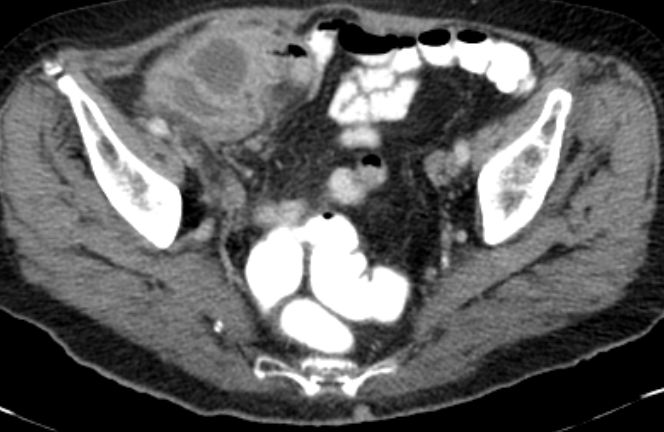

71-jährige Frau mit Adenokarzinom der Appendix pT4b pNo Mo Lo Vo.

Coloskopie: zirkuläres, exophytisch und ulzerierend wachsendes Karzinom mit einer Größe von 60 mm im Colon ascendens, nicht passierbar.![]() |

![]() |

Unmittelbar oberhalb der Ileozökalklappe Nachweis eines 7 x 6 cm großen, schüsselförmig exulzerierten Tumors.

Der Tumor durchdringt alle Wandschichten und infiltriert retrograd den davor geschalteten Dünndarm.![]() |